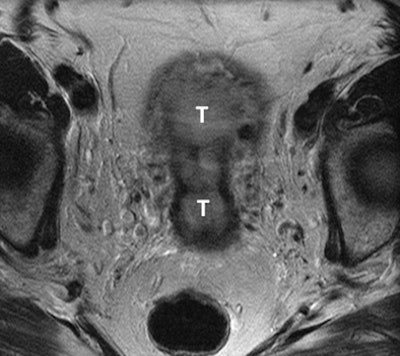

| MR image of a 67-year-old woman shows tumors (T) of intermediate signal intensity in both the endometrial cavity and cervix. The primary origin could not be determined from the MRI scan. Final pathologic diagnosis from the hysterectomy specimen was papillary serous carcinoma of the endometrium with deep myometrial and cervical stromal involvement. |